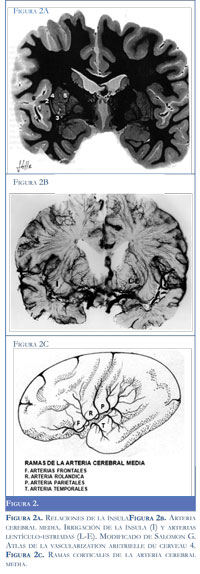

La ínsula (Figuras 1 y 2): es una amplia zona de la corteza cerebral cubierta por los opérculos frontal, parietal y temporal de la fisura de Silvio. Si retiramos estos opérculos aparece la corteza de la ínsula en toda su extensión. Tiene una forma triangular con un vértice inferior. Está limitada por el surco peri-insular que se divide en tres porciones: el surco peri-insular anterior que la separa del lóbulo frontal, el surco peri-insular superior que la separa de las cortezas frontal y parietal, y el surco peri-insular inferior que la limita con el lóbulo temporal. Un surco medio que se extiende desde su vértice inferior hasta la parte media del surco peri-insular superior, la divide en dos mitades, anterior y posterior; en la mitad anterior se aprecian tres giros cortos y en la posterior tres giro largos que convergen hacia el vértice inferior (Figura 1) La porción inferior de la mitad anterior de la ínsula es más prominente que el resto de ella y recibe el nombre del polo, entre este y la convergencia de los giros largos se aprecia un reborde arqueado conocido como limen de la ínsula, que se continua en la base del cerebro con el canal silviano o vallécula; el polo a su vez se continua en las base del cerebro con el giro transverso de la ínsula (2).

Irrigación de la ínsula y estructuras subyacentes (Figuras 2a y 2b). Luego de su origen la arteria cerebral media (ACM) se dirige lateralmente por el canal silviano y pronto se divide en dos ramas; una de ellas da ramas terminales ascendentes que emergen por el limen de la ínsula y la fisura de Silvio para distribuirse en la corteza de los lóbulos frontal y parietal son las arterias frontopolar, precentral, rolándica postcentral y angular (Figura 2c). La otra rama de división de la ACM origina las arterias temporales que se distribuyen en el lóbulo temporal. La arteria rolándica recorre la superficie de la ínsula por el surco medio, o en su vecindad, y pasa luego a la fisura central (de Rolando) para dar irrigación los giro pre y post-central. Sobre la ínsula la arteria rolándica da una pequeña rama que se ramifica en pequeñas arteriolas para la corteza insular y estructuras subyacentes. Varnavas y cols (3, 4) anotan que son entre 100 y 125 arteriolas insulares con un diámetro de 0.1 y 0.2 mm que dan irrigación a la corteza en el 90% de los casos; en un pequeño porcentaje de casos una arteria temporal puede dar irrigación a parte de los giros largos de la ínsula.

La ACM en su trayecto por el canal silviano origina varias arterias perforantes, las arterias lentí-culo-estriadas. Estas son 10 a 14 delgadas arteriolas (5), con un diámetro aproximado de 0.5 mm, que penetran al cerebro por su base para dar irrigación al núcleo lenticular, en especial al putamen, a la cabeza del núcleo caudado, a la parte anterior de la cápsula interna y al centro semioval correspondiente del lóbulo frontal. En las imágenes de Salomon (4) obtenidas con inyección de material radio-opaco se pueden observar claramente las arteriolas insulares de la arteria rolándica y la distribución de las arterias lentículo-estriadas (Figura 2b).